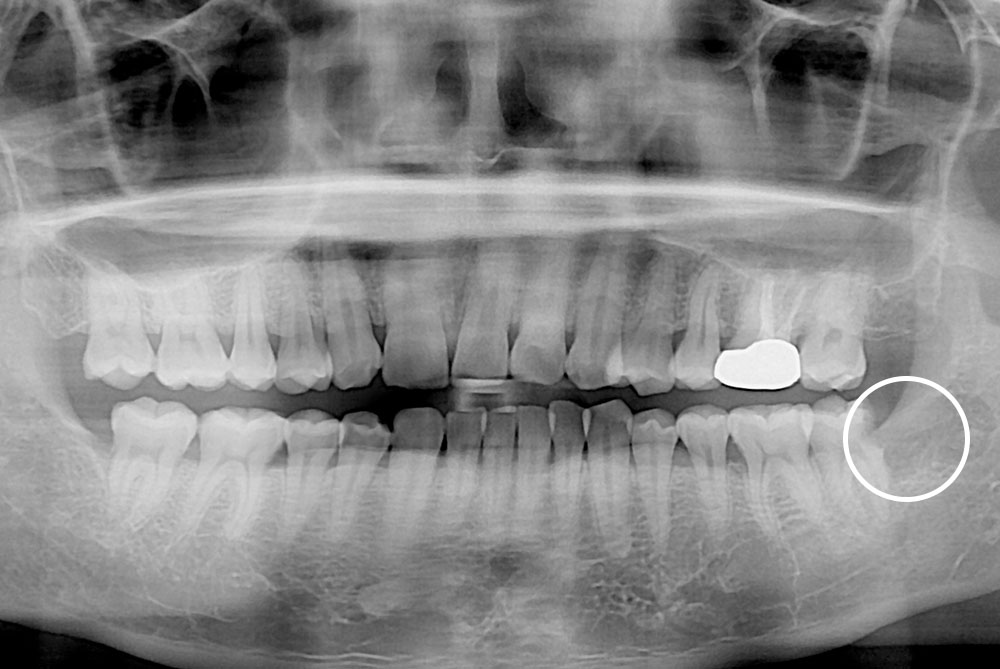

[사랑니] 매복 사랑니 발치

치료전 : 2019-09-27

세종치과는 구강악안면외과학 박사이신 원장님이 발치하는 치과입니다.